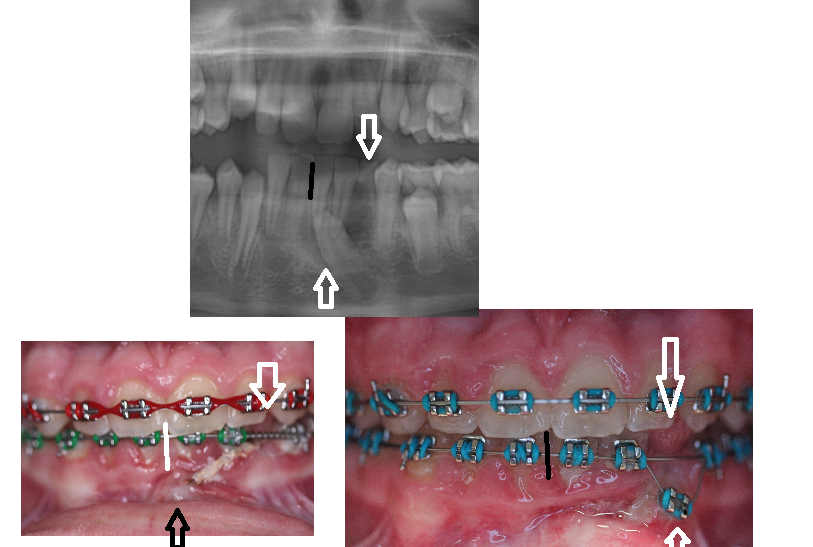

Although Dr. Lenk has the education and experience to fix problems like this, IF DR LENK HAD SEEN THIS PATIENT EARLY SHE COULD HAVE PROVIDED RECOMMENDATIONS TO PREVENT YEARS OF COMPLEX CARE.